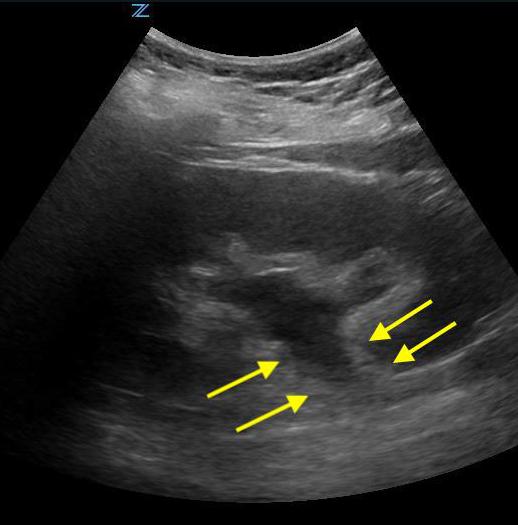

- Figure 2. Moderate hydronephrosis demonstrating location of ureter (surrounded by arrows) exiting renal pelvis

- Videos 11-13. Mild hydronephrosis

- Videos 14-15. Moderate hydronephrosis

- Video 16. Moderate to severe hydronephrosis

- Video 17. Severe hydronephrosis